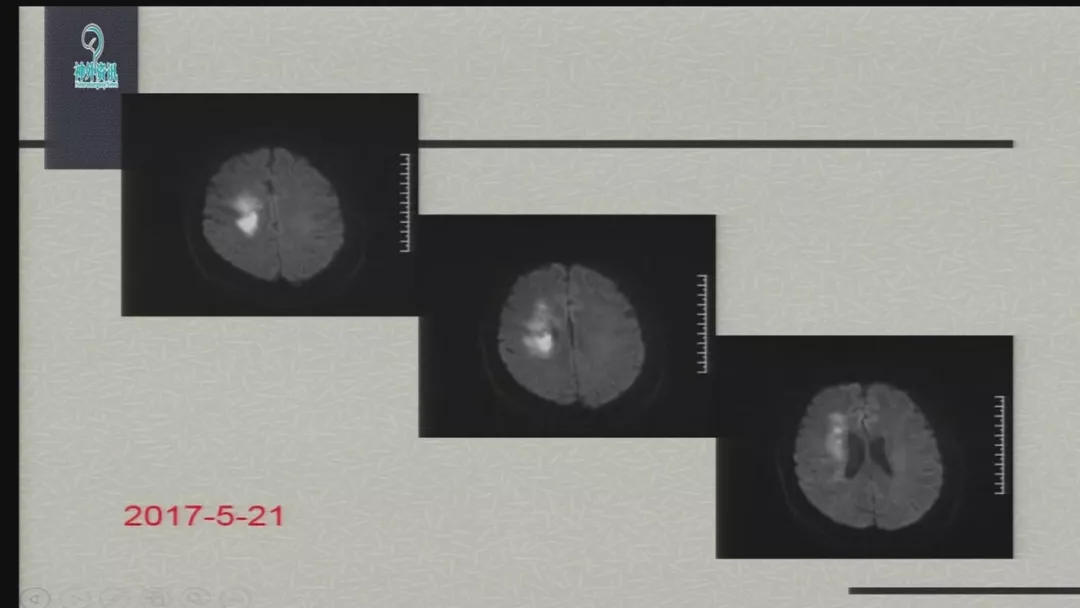

今天为大家分享的是由郑大一附院徐浩文教授在第七届全国介入医学工程大会上带来的“Neuroform EZ在ICAD治疗中的应用”精彩讲课视频和PPT,欢迎观看!(内容未经讲者审核,不当之处请与我们联系)